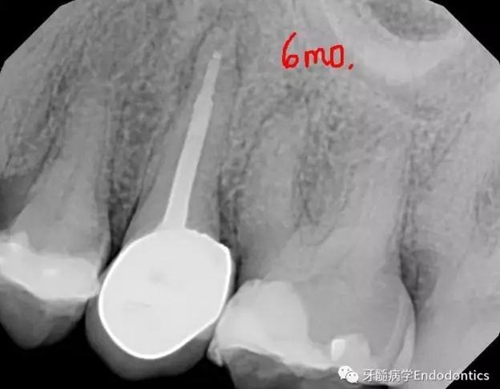

圖4.術后6個月